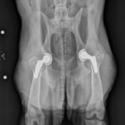

This case report demonstrates how Tekscan's Walkway allowed for objective evaluation of changing limb use as the total hip replacements were performed on a dog.